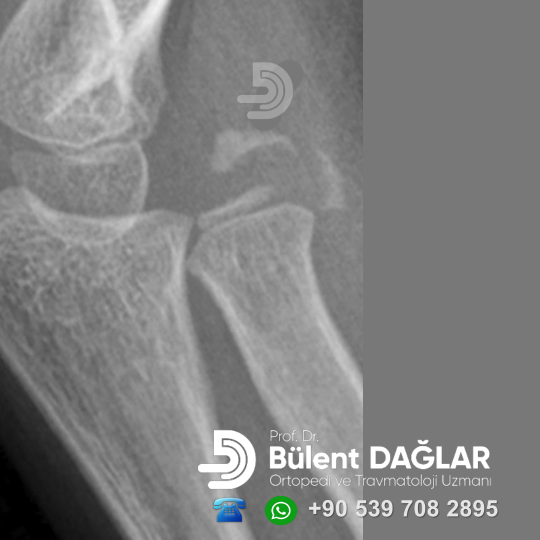

Çocuklarda Dirsek Ekleminde Heterotopik Ossifikasyon Oğlum 3 ay önce düştü. Dirsekte basit bir kırık oldu. Alçı ile tedavi edildi. Alçı…